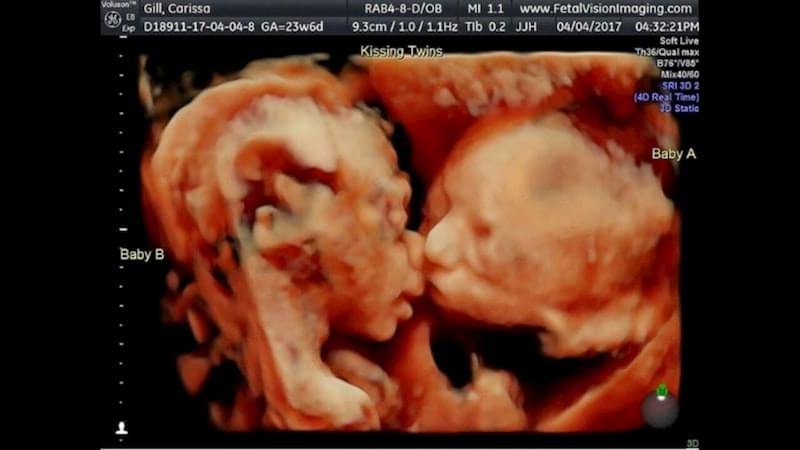

Двуплодная беременность опасна, если запоздает начало деления яйцеклеток, вплоть до 13 суток. У таких плодов на двоих один общий хорион и амниотический мешок, они соприкасаются друг с другом. При неудачном стечении обстоятельств плоды сращиваются: зарождаются либо сиамские близнецы, либо дети имеют на двоих один орган (конечность).